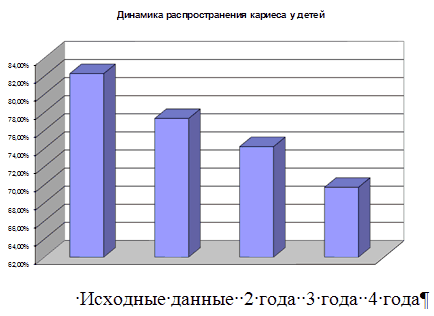

Чтобы профилактика давала наибольший эффект, необходимо одновременно воздействовать на все основные факторы риска в развитии зубов. Профилактика кариеса зубов препаратами фтора получила наибольшее распространение в мире, это - единственный метод, позволивший достичь реального снижения заболеваемости.

Но на территории Р.Ф. существуют и другие проекты, которые могут решить эту проблему. Например, в Воронежской началась программа создания фторосодерщащего молока. В результате которой стоматологические заболевания сократились